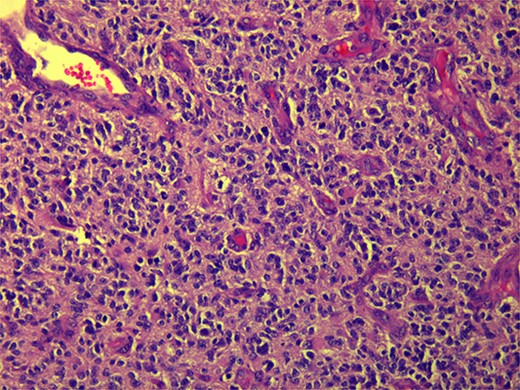

CT and PET scans revealed multiple positive lymph nodes, but metastatic lesions were not found in chest, abdominal organs, or bone (Fig. 2). Genetic and molecular tests revealed wild rat associated sarcoma, wild BRAF, proficient MMR, and negative HER-2. Tumor markers were positive. The patient started chemotherapy, which included CAPOX, cetuximab, and FOLFOX. PET scan was done for re-evaluation, and marked partial disease response was observed with currently no evidence of disease. After that, the patient started to experience reversible amnesia, bizarre behavior followed by right side upper limb weakness, hyperreflexia on the right side, positive Babinski sign on the left, and positive Hoffman sign bilaterally. Brain MRI was done, which revealed a left fronto-parietal extra-axial space-occupying lesion with vasogenic edema and midline shift (Fig. 3). Patient underwent brain lesion resection through left fronto-parietal craniotomy. The pathology revealed GBM (Fig. 4). IHC stain of neoplastic cells showed wild IDH and positive for GFAP, and 30% of the neoplastic cells showed positive for Ki67.

Diagnosis of GBM occurs after new-onset seizure or neurology deficit. Histopathology shows necrosis and microvascular proliferation, high mitotic rates, anaplasia, and invasiveness. Clinical diagnosis includes brain imaging. Immunohistochemistry markers antibody selectively detects mutant IDH1R132H [5]. However, CRC is asymptomatic until it reaches an advanced stage. Investigations by colonoscopy are the method of choice [6].